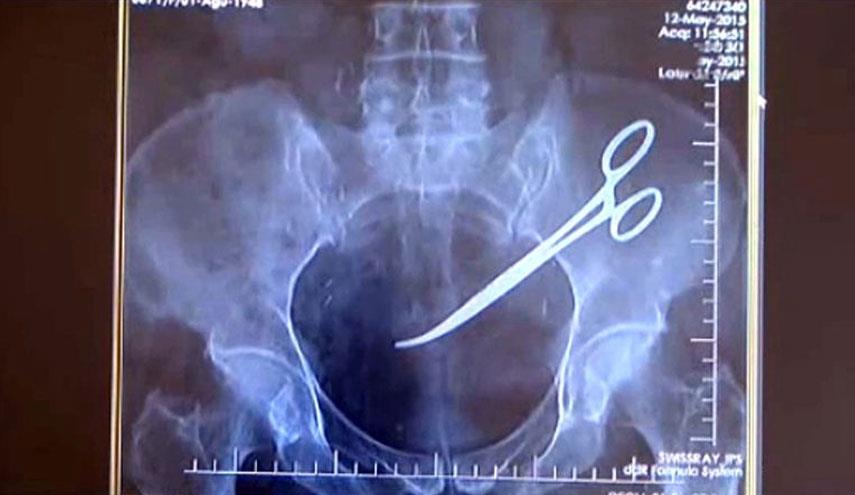

صدق او لا تصدق..بعد 34 سنة يتم إخراج مقص من أمعاء مريض!

العراق-الكوثر: كشف مصدر طبي في محافظة أربيل شمال العراق، الاربعاء، انه تم إخراج مقص طبي من داخل إمعاء أحد المرضى بعد 34 سنة من إجرائه عملية للمعدة.